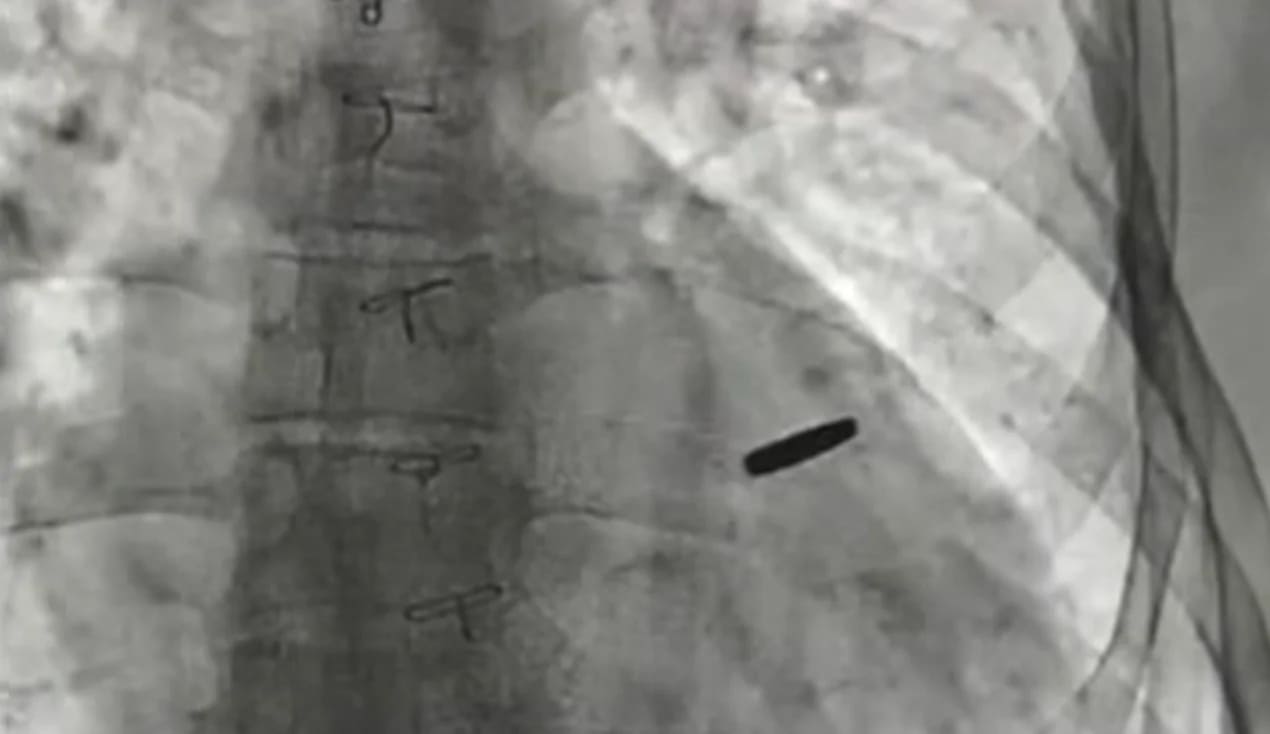

Фото из российских СМИ

Попытавшись прорваться из окружения на территории металлургического комбината имени Ильича, он получил ранение: пуля пробила бронежилет и попала в грудную клетку. Это ранение фактически спасло ему жизнь – из-за него он не попал в колонну, которая пошла на прорыв и была почти полностью уничтожена.

Несмотря на ранение, Артем продолжал оказывать медицинскую помощь в бункерах металлургического комбината «Азовсталь». В мае 2022 года он вместе с другими защитниками и защитницами вышел оттуда по приказу командования и оказался в плену у российских военных.

В 2025 году Артема освободили во время обмена в День Независимости Украины. В плену он провёл почти три года. Уже после возвращения украинские врачи выяснили: пуля, от которой Артем получил ранение ещё в Мариуполе, всё это время находилась в области сердца. Его успешно прооперировали.